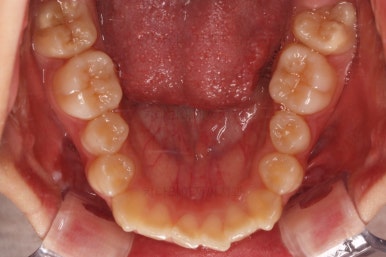

연산동치과 초진 시, 입안의 모습입니다.

보시다시피 앞니쪽이 많이 삐뚤고요. 어금니쪽이 긴밀하지 못한 부정교합이 있네요.